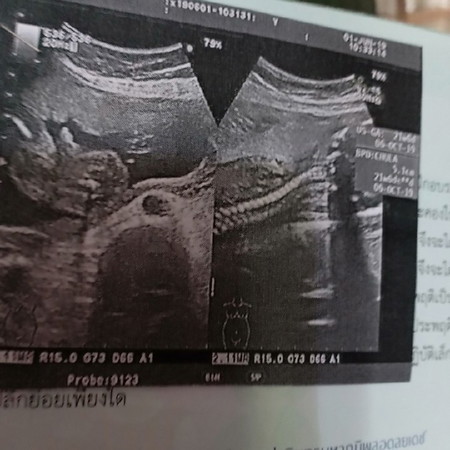

แม่ๆไปซาวด์ตอน21วีค หมอบอกเพศเชื่อได้กี่%ค่ะบ้านนี้ หมอบอกว่าไม่ถึง100% แสดงว่าอาจจะมีการเปลี่ยนอีกใช่ไหมค่ะ รอคำตอบจากแม่อยู่นะคะ??

แบบในรุปฝั่งซ้าย หมอบอกว่าผู้ชายแต่ไม่100%ค่ะ